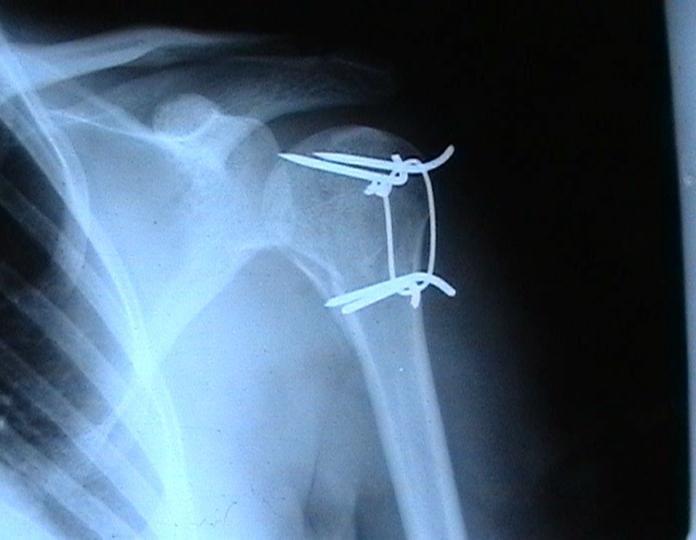

Переломовывих плеча сложная проблема и технически не уверен как для коллег, но для меня сколько я не встречался, технически сложно *вытянуть* вывихнутую головку из-под впадины. Последнее время не применяю пластины для фиксации перелома, а использую спицы и проволочную петлю (тем более часто и густо спонгиозные винты не держатся в головке прочно).

Момент , который следует учитывать при использовании такого рода фиксации - необходимо быть уверенным , что спицы не проникают в сустав, поэтому полезно пользоваться ЭОпом для контроля или интраоперационными рентгенограммами

перед ушиванием раны.

Фиксация получается достаточно стабильная, правда мои заключения основаны только на клинических наблюдениях, возможности протестировать прочность фиксации в лабораторных условиях нет. Я не автор данного типа фиксации в основе его лежит принцип напряженной фиксации (Weber tension Band fixation). Когда-то у нас использовали фиксатор проф Сеппо при переломах

шейки бедра - принцип работы аналогичен, только менее громоздкие элементы конструкции и более доступные для применения в любых условиях.

Не происходит ли миграция спиц?

Я использую обычные 2 мм спицы и пока в 8 случаях , что применял подобную фиксацию миграции не было, хотя вполне вероятна такая возможность и видимо оптимальнее использовать спицы с резьбой на конце, что должно предотвратить потенциальный риск миграции. Хотя если спица начинает пальпироваться под кожей и доставлять неудобство больному, то её легко удалить в условиях перевязочной. На мой взгляд миграция спицы мложет произойти только тогда,

когда пациент начинает активно работать рукой, к этому времени перелом уже срастется, поэтому опасности скомпрометировать стабильность фиксации уже не будет.

Почему нельзя использовать только проволоку (сформировав для этого туннели в проксимальном и дистальном фрагменте ).

Я такой же практик как и Вы, поэтому решать можно или нельзя использовать только проволочную петлю решать Вам, хотя на мой взгляд, обычная проволочная петля не создает многоплоскостной стабильности фиксации, а только лишь в плоскости проведенных отверстий в проксимальном и дистальном фрагментах и другой момент зачастую такие переломы случаются у пожилых людей с порозной костью, тогда, как понимаете, проволочная петля может легко прорезаться через кость и не о какой стабильной фиксации уже речи быть не может в то время как спицы держаться в порозной кости тем более, что при такой фиксации создается момент силы, направленный не на вытягивание спицы из кости.